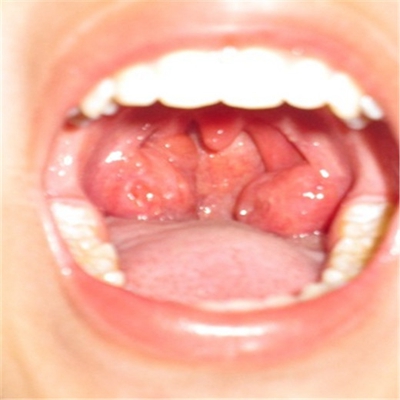

扁桃體惡性腫瘤圖片

扁桃體癌圖 (7)

扁桃體癌圖 (8)